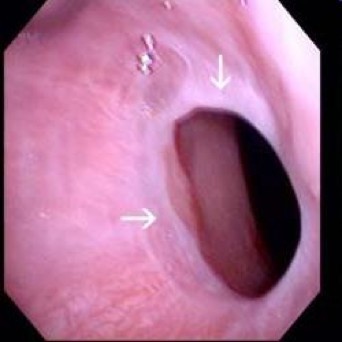

A 40 year old woman comes to her doctor complaining of difficulty swallowing. Additionally, she has increased bruising and her periods have gotten heavier. Based on the endoscopic image below, what is her diagosis?

Esophageal web= eccentric, thin membrane of tissue in esophagus, most commonly proximal. Can cause dysphagia, aspiration

Plummer-Vinson syndrome= esophageal webs + iron deficiency anemia + glossitis; seen in women, responds to iron supplementation